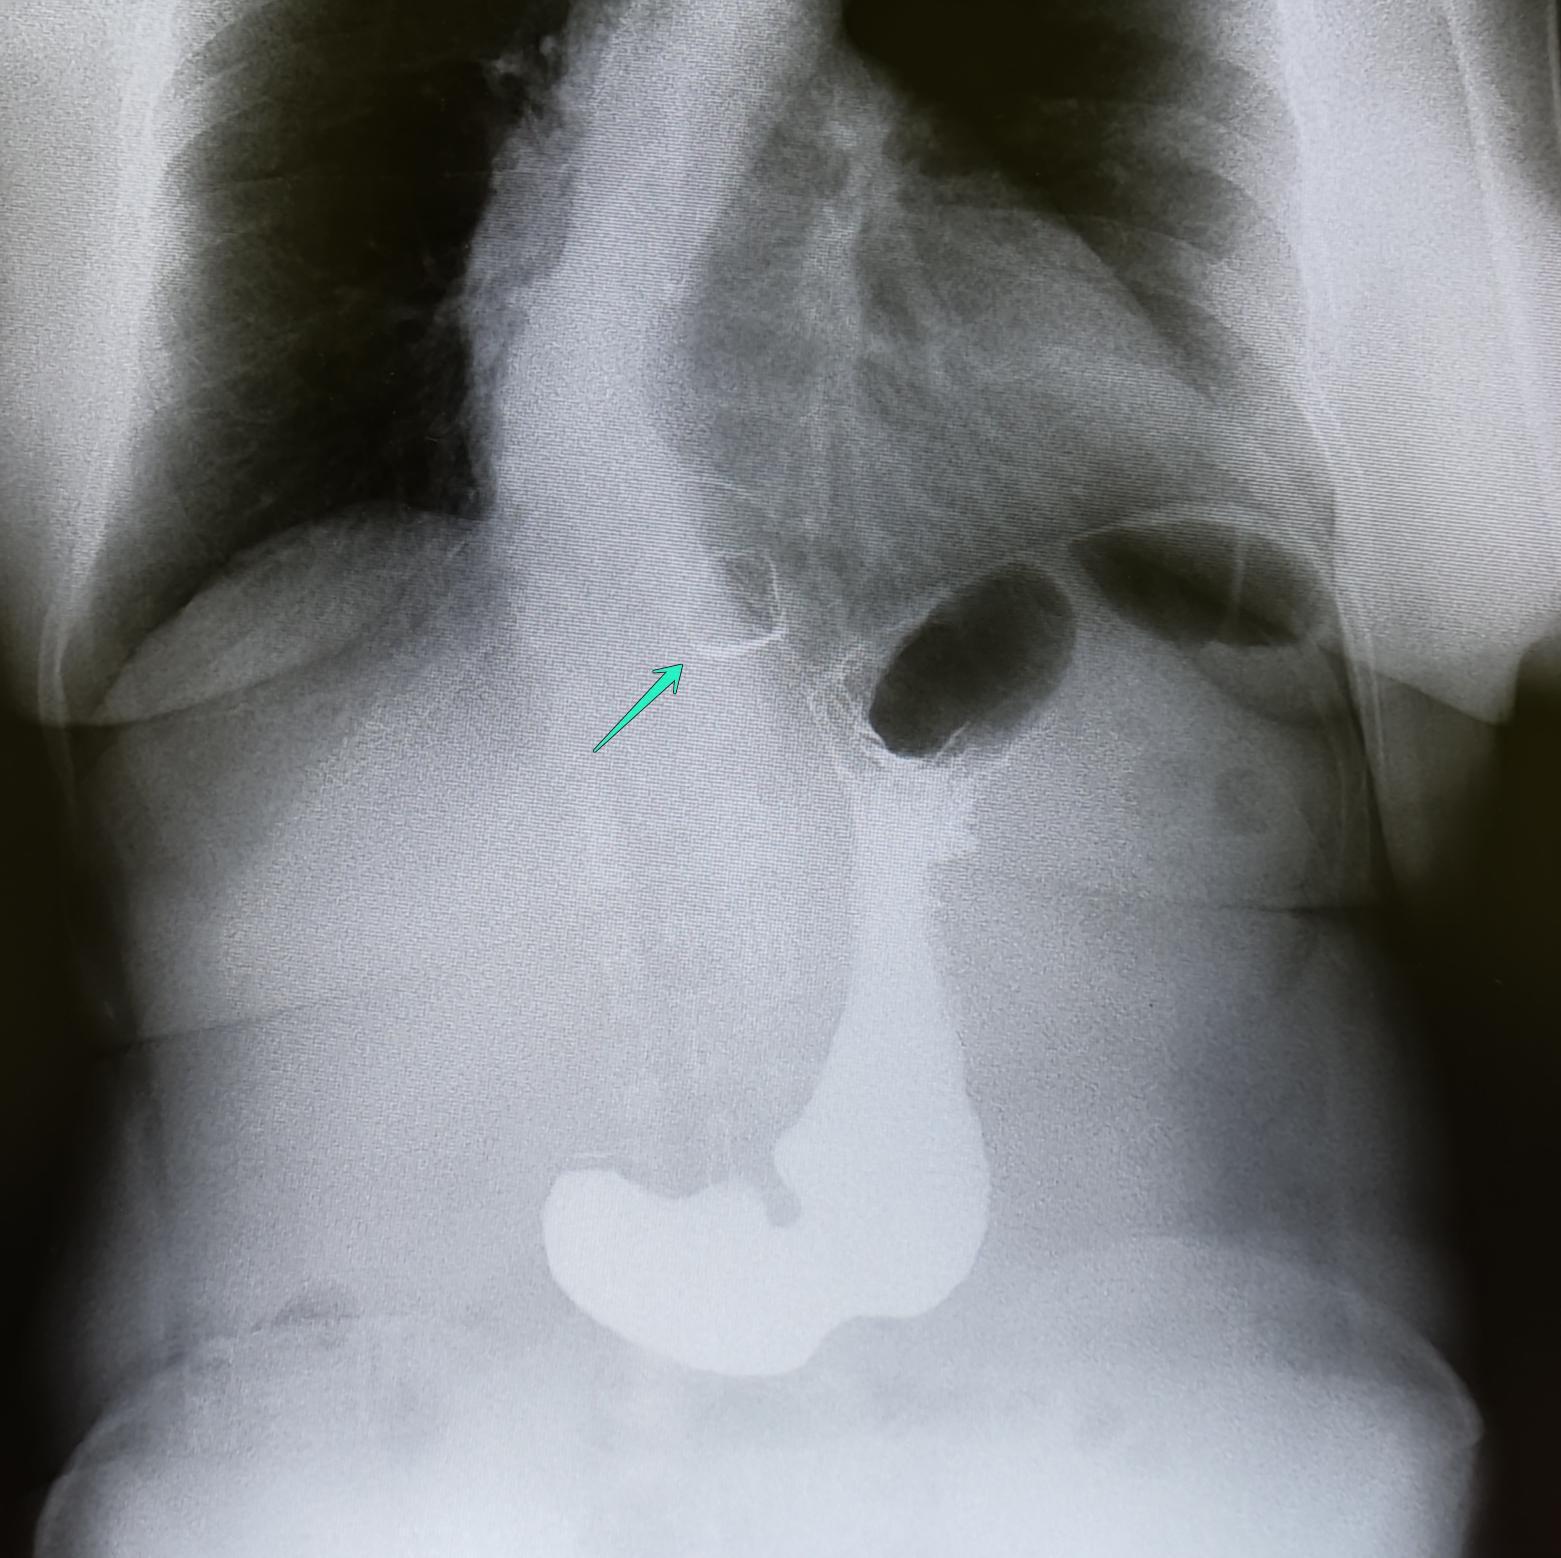

Диагностика ГПОД:ФГДС, МРТ ОБП, Рентгеноскопия желудка(для определения степени ГПОД-выполняется Р-скопия желудка в положении Тренделенбурга).

Описание: на рентгеноскопии желудка положении Тренделенбурга -над диафрагмой находится мешковидно расширенный брюшной сегмент пищевода, кардия расположена на уровне диафрагмы. Заключение: ГПОД 1ст

По 565 постановлению, I ст. ГПОД- над диафрагмой находится брюшной сегмент пищевода, кардия расположена на уровне диафрагмы.